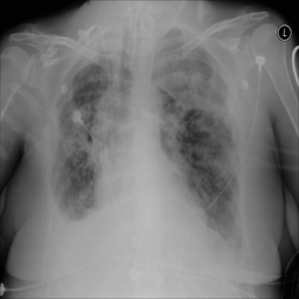

4.3.2 Localized Disease Induction

Finally, a key requirement of counterfactual visual attribution is sensitivity to both exogenous and endogenous aspects of disease: we define the endogenous visual aspects of disease as those attributes intrinsic to diagnosis, and the exogenous aspects as free-parameters associated with diseased tissue that are not themselves directly implicated in diagnosis. An example might be a tumor identified via its texture characteristics (endogenous), but which is otherwise located arbitrarily within a particular organ (so that location within the diseased organ is effectively an exogenous free variable within a VA context).

We therefore illustratively test our model in regard to its latent capability to induce disease in specific locations through the simple expedient of conditioning on positionally-indicative text. The results may be seen in figure 7 for the case of localized lung opacity (lung opacity being chosen because it is both diffuse and generally specific to one or other lung). The respective condition texts are “large lung opacity on the left” and “large lung opacity on the right”.